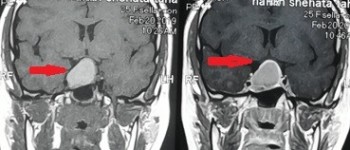

skull tumor compressing the right optic nerve